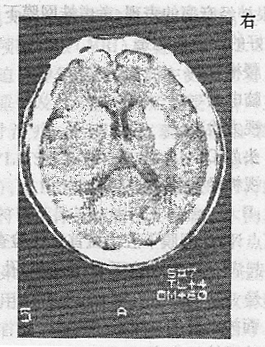

男性,56岁。高血压病患者。旅游登山中突然左侧肢体发麻、乏力。急送医院,摄头颅CT片如下图。

最可能的诊断是()